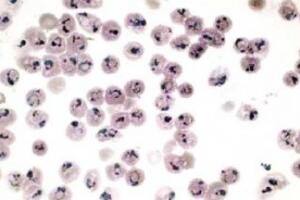

Parasitología

Agresividad oculta

Echa por tierra la idea de que exista una forma benigna de paludismo